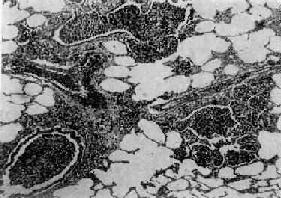

图9-19 支气管肺炎 图中见灶状实变的肺组织,肺泡内充满以中性粒细胞为主的炎性渗出物;病灶中有发炎的细支气管 【并发症】 小叶性肺炎发生并发症的危险性比大叶性肺炎大得多。可并发心力衰竭、呼吸衰竭、脓毒败血症、肺脓肿及脓胸等。支气管破坏较重且病程较长者,可导致支气管扩张。 【临床病理联系】 因小叶性肺炎多为其他疾病的并发症,其临床症状常为原发性疾病所掩盖。由于支气管粘膜的炎症刺激而引起咳嗽,痰呈粘液脓性。因病变常呈灶性散布,肺实变体征一般不明显。病变区细支管和肺泡内含有渗出物,听诊可闻湿啰音。X线检查,可见肺野内散在不规则小片状或斑点状模糊阴影。本病发现及时,治疗得当,肺内渗出物可完全吸收而痊愈。但在幼儿,年老体弱者,特别是并发于其他严重疾病时,预后大多不良。 (二)病毒性肺炎 病毒性肺炎(viral pneumonia)常常是因上呼吸道病毒感染向下蔓延所致。患者多为儿童,症状轻、重不等,但婴幼儿和老年患者病情较重。一般多为散发,偶可酿成流行。引起肺炎的病毒种类较多,常见的是流感病毒、还有呼吸道合胞病毒、腺病毒、副流感病毒、麻疹病毒、巨细胞病毒等等,也可由一种以上病毒混合感染并可继发细菌感染。病毒性肺炎的病情、病变类型及其严重程度常有很大差别。 【病理变化】 早期或轻型病毒性肺炎表现为间质性肺炎,炎症从支气管、细支气管开始,沿肺间质发展,支气管、细支气管壁及其周围、小叶间隔以及肺泡壁等肺间质充血、水肿,有一些淋巴细胞和单核细胞浸润,肺泡壁明显增宽(图9-20)。肺泡腔内一般无渗出物或仅有少量浆液。病变较重者,肺泡也可受累,出现由浆液、少量纤维蛋白、红细胞及巨噬细胞组成的炎性渗出物,甚至可发生组织坏死。有些病毒性肺炎(如流感病毒肺炎,麻疹病毒肺炎、腺病毒肺炎等)肺泡腔内渗出较明显,渗出物浓缩凝结成一层红染的膜样物贴附于肺泡内表面,即透明膜形成。支气管上皮的肺泡上皮也可增生,甚至形成多核巨细胞。麻疹病毒肺炎的病变特点为在间质性肺炎的基础上,肺泡壁上有透明膜形成,并有较多的多核巨细胞(巨细胞肺炎),在增生的上皮细胞和多核巨细胞的胞浆内和胞核内可检见病毒包含体。病毒包含体常呈球形,约红细胞大小,呈嗜酸性染色,均质或细颗粒状,其周围常有一清晰的透明晕。其他一些病毒性肺炎也可在增生的支气管上皮、支气管粘液腺上皮或肺泡上皮细胞内检见病毒包含体。如腺病毒肺炎可在增生的上皮细胞核内(图9-21),呼吸道合胞病毒肺炎可在增生的上皮细胞胞浆内,巨细胞病毒肺炎也可在增生的上皮细胞核内检见病毒包含体。检见包含体是病理组织学诊断病毒性肺炎的重要依据。

图9-20 间质性肺炎 肺泡壁及细支气管周围肺间质内有大量炎性细胞(主为单核细胞)浸润。肺泡壁明显增宽。肺泡腔内无渗出物